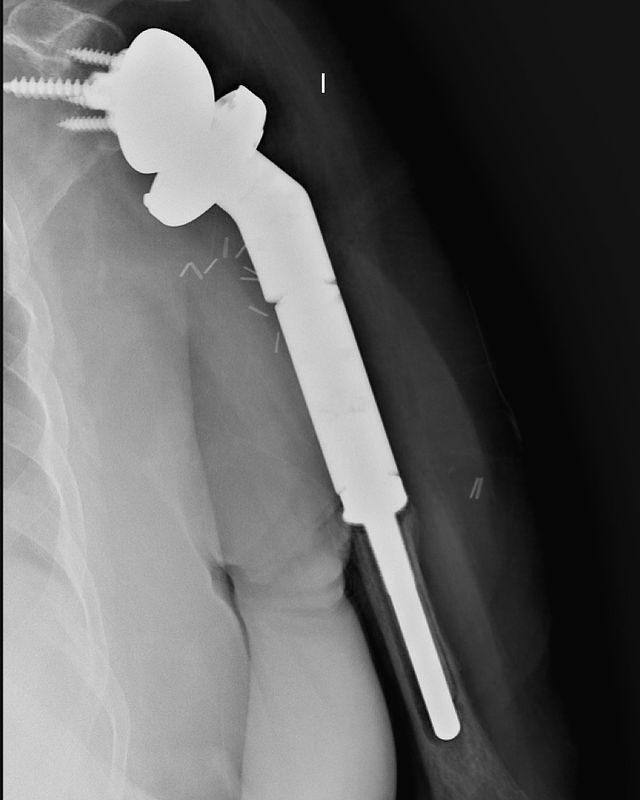

Condrosarcoma en húmero

Hoy me gustaría compartir el caso de una mujer de 72 años con un condrosarcoma G3 de humero izquierdo (imágenes 1,2),  a quien hace 1 año se le realizó una resección (imagen 3) y reconstrucción con la megaprótesis invertida Comprehensive SRS cementada de Zimmer Biomet. (imagen 4) Radiografía de control (5). A los 6 meses presenta un aflojamiento aséptico (imagen 6). Retiramos el componente humeral (imagen 7) y reconstruimos con un ALOINJERTO TELESCOPICO PRESSFIT (imagen 8) y un nuevo componente humeral mas corto (imagen 9) Radiografías de la reconstrucción AloProtésica (imagen 10)

Para poder ayudar a los pacientes con sarcomas debemos tener múltiples opciones reconstructivas, ya sea para el procedimiento inicial, como para las complicaciones que puedan surgir